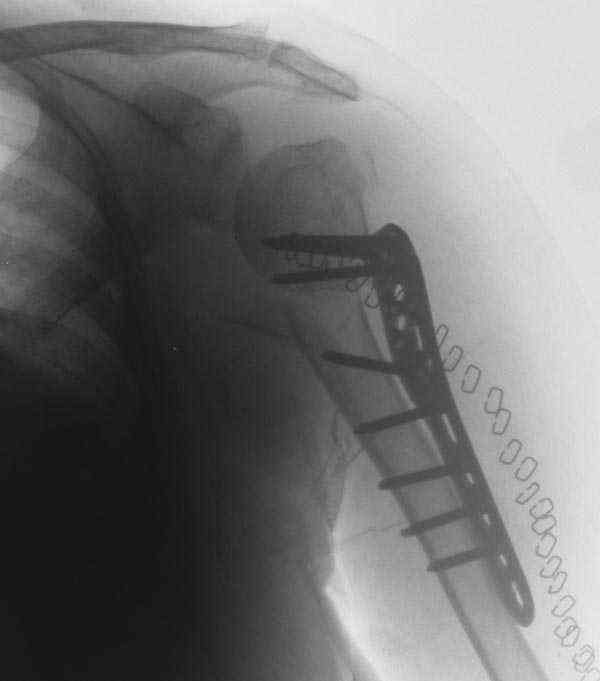

I am attaching the radiographs of the mother of a doctor. She has chronic renal failure for >10 years, diabetes mellitus and coronary artery disease. Age 62. She was offered the options of non-surgical management in a sling and surgery with a locking plate. She was given Tramadol for pain relief. Five days after injury, patient requested surgery, because of pain, inability to move without pain.

The reduction is not perfect. The patient is very small made, and it was difficult to bring the plate proximally without impingement in abduction.

Pain relief after surgery was early and sustained.

I agree that this reduction is not perfect. The gap may later result with nonunion. Such or even better reduction can be reached without site

opening as you mentioned. Locking plates are positioned as less invasive, why so long incision was - even longer than plate?

Pls compare wound size visible at x-rays of your example with ones after typical closed nailing of the proximal humerus.